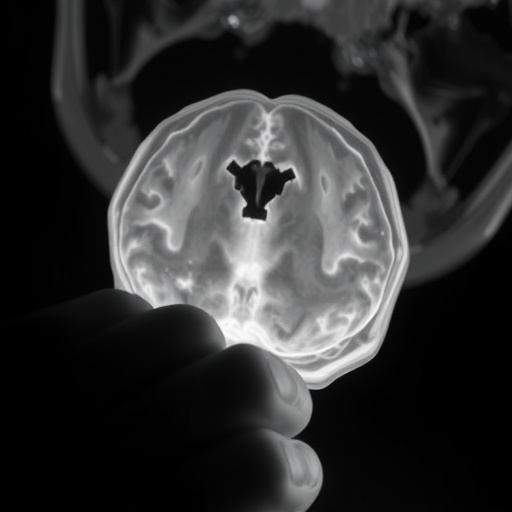

In the complex and critical field of neonatal medicine, precise language and uniform criteria are indispensable to advancing research and improving outcomes for the most vulnerable patients—newborns suffering from brain injuries linked to oxygen deprivation. A groundbreaking systematic review published recently in Pediatric Research confronts a pervasive and often overlooked problem: the inconsistency and lack of standardization in terminology, diagnostic definitions, and eligibility criteria across clinical trials concerning neonatal encephalopathy, hypoxic-ischemic encephalopathy (HIE), and perinatal asphyxia. This meticulous analysis by Hurley, Quirke, Branagan, and colleagues offers a clarion call for harmonizing the language and frameworks used in this crucial research area.

Neonatal encephalopathy broadly refers to a syndrome of disturbed neurological function in newborns, manifesting as altered consciousness, abnormal muscle tone, and seizures, frequently caused by hypoxic or ischemic events during the perinatal period. Despite its widespread clinical relevance, the terms ‘neonatal encephalopathy,’ ‘hypoxic-ischemic encephalopathy,’ and ‘perinatal asphyxia’ are often used interchangeably or inconsistently in research, which undermines the comparability of studies and the synthesis of evidence necessary for clinical advances. The comprehensive review scrutinizes how leading clinical trials define these entities, revealing a fragmented landscape riddled with variability and ambiguity.